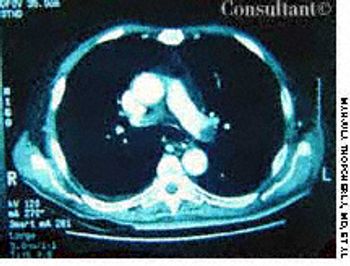

A 64-year-old woman with a history of diabetes, hypertension, and lymphoma was admitted to the hospital with a dull headache, conjunctival congestion, and slight dyspnea. Her pulse rate was 96 beats per minute; blood pressure, 146/68 mm Hg; and respiration rate, 22 breaths per minute. She also had increased jugular venous distention; cardiovascular and chest examination findings were normal. Edema of both arms and dilated blood vessels on the anterior chest wall were noted.